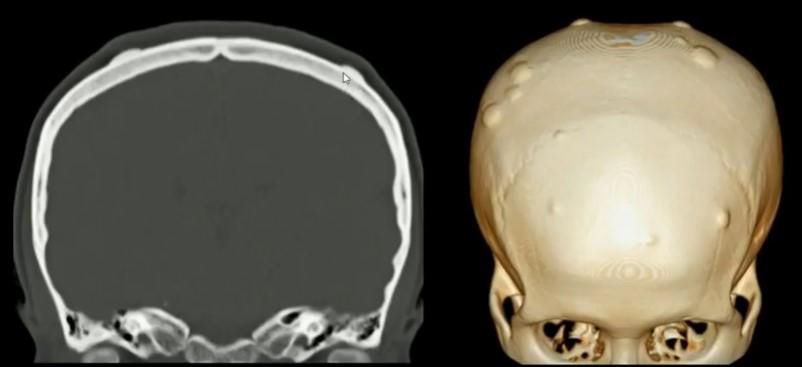

Типи пухлин кісток черепа

Пухлини кісток черепа бувають первинними та вторинними. Найчастіше вражаються кістки лицьового скелета, набагато рідше – кістки склепіння та основи черепа.

Первинні пухлини кісток черепа ростуть з клітин кісток черепа і його оболонок.